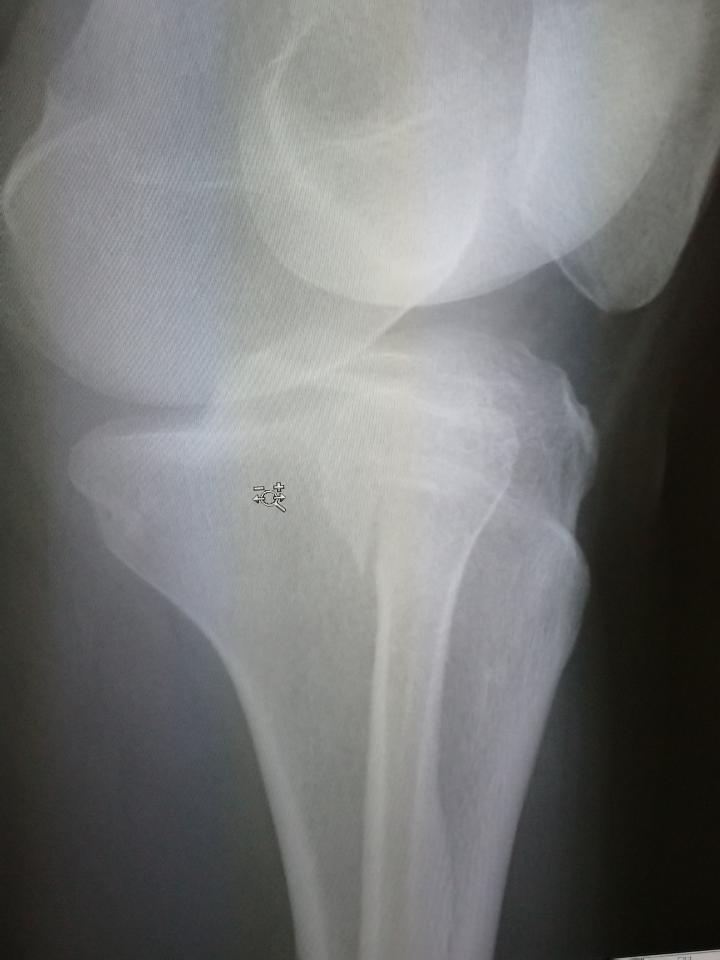

私は自分の不注意で

左足を骨折してしまいました

レントゲンを撮り

肺炎が酷くなり